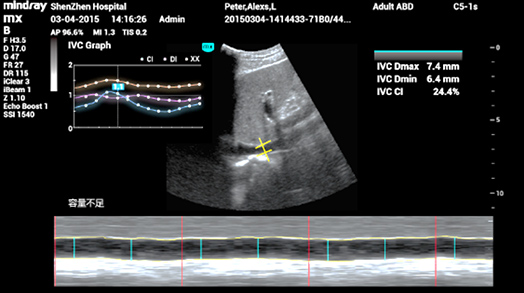

3Smart IVC

La medici├│n autom├Ītica de los par├Īmetros de la VCI (vena cava inferior) ayuda a evaluar el estado del volumen y gu├Ła la terapia de fluidos. Gr├Īfico de cambio de par├Īmetros sobre CI o DI e IVCV para monitorear el cambio de pacientes en estado cr├Łtico.

3